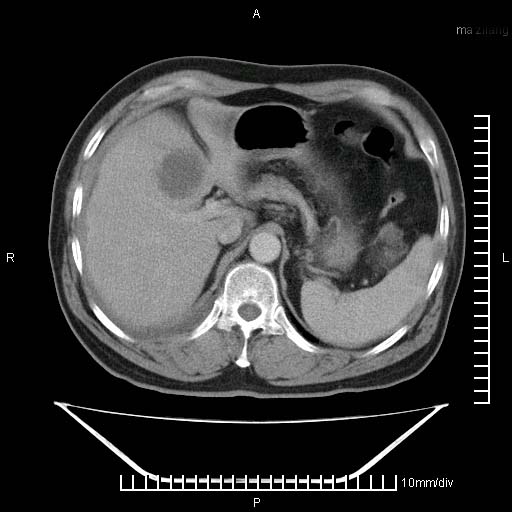

标题: CT25082:肝脏增强:男性,70岁 [打印本页]

标题: CT25082:肝脏增强:男性,70岁

患者以心脏疾病收住院,腹部无明显症状,b超查肝脏有占位。

增强效果不理想。考虑转移,胆囊壁明显增厚,不排除胆囊癌肝转移。

病灶无强化,考虑囊肿。

牛眼征,中心坏死无强化,外缘强化,最外缘又见低密度,考虑转移,与脓肿鉴别

肝内多发转移瘤,右下肺炎症并少量胸水。胃壁增厚建议胃镜,胰尾部“病变”为肠管。

1)肝脏多发性转移瘤(不排除胰尾癌转移所致可能)。2)腹水。3)右侧少量胸腔积液。

ct25082 结果:转移瘤

外院mr结果:胰尾恶性占位。